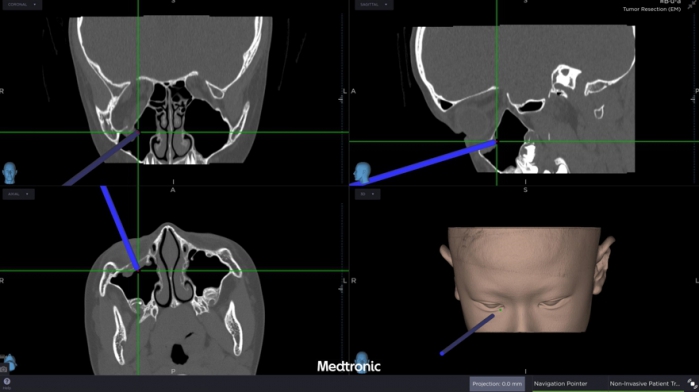

經評估後,中山醫學大學附設醫院口腔顎面外科醫療團隊邱昱瑋主治醫師、張芳語主治醫師及洪珮瑄主治醫師,立即制定手術方案,運用創新電腦數位模擬技術,術中搭配內視鏡與精密導航系統,精準定位眼底嵌頓肌肉的位置,成功將被夾住的眼底肌肉復位。術後,患者複視症狀消失,眼球活動恢復正常,並未留下相關併發症,順利重拾日常生活與學習品質。

中山附醫口腔顎面外科張芳語主治醫師補充,重建受損眼眶骨在臨床上挑戰重重,包括手術視野狹小、骨頭型態複雜、手術精準度要求高,以及術後疤痕與外觀重建的考量,透過精準的數位導航技術,醫師團隊能克服這些困難,幫助患者安全恢復功能與外觀,重拾自信與生活品質。洪珮瑄醫師則強調,對於兒童患者而言,手術精準度與微創性格外重要,不僅要恢復功能,更要兼顧未來面容發育的完整性;該起案例不僅展現數位導航手術在顏面骨折治療上的價值,也提醒家長與學校,即便外觀無傷痕,一旦出現眼球運動受限或複視症狀,應立即就醫,避免錯過黃金治療期。